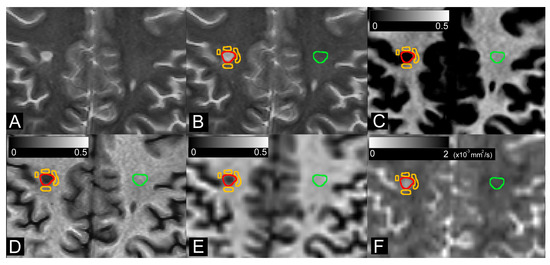

2.7. Image Analysis